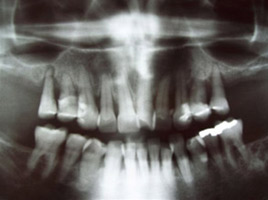

poslije